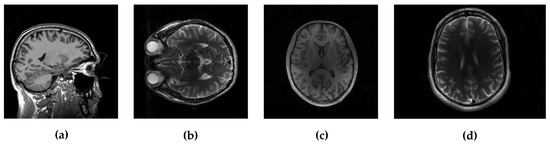

In the experimental evaluation we used different MRI images, starting from high-resolution MRI images, shown in Figure 2, and using real data acquired in k-space. For the following experiments, we used simulated sampling trajectories on a Cartesian grid with different sampling rates, except for the last experiment, when the measurements are undersampled with the non-Cartesian radial sampling trajectory used in a real scan. First, we consider reconstruction of MR image magnitude for different sampling rate (SR) obtained using various sampling trajectories. For this we utilize dataset of 248 T1 MRI brain slices acquired on a Cartesian grid at Ghent University hospital (one sagittal slice is presented in Figure 2). Then we focus on the reconstruction of complex MR images from single and multi-coil undersampled measurements. Complex T2-weighted brain images axial-1, axial-3 from [31] and [38] respectively (their magnitudes are presented in Figure 2) are used in experiments for the reconstruction of single-coil complex images while the T1-weighted brain image axial-2 [38] is used in the multi-coil reconstruction experiment. We also present the reconstruction results on real radially acquired measurements in k-space on non-Cartesian grid. These data, consisting of the acquisitions of a pomelo fruit were supplied by the Bioimaging Lab in Antwerp. In our experiments for sparse signal representation we used the non-decimated wavelet transform with 3 scales. For comparison, we report the results of LaSAL and LaSAL2 from [29], FCSA [5], FCSANL [39] and WaTMRI [25] with the original implementations. All these methods, except LaSAL, employ a compound regularization. The reconstruction results for complex images from single-coil and multi-coil measurements, are compared with the corresponding results of pFISTA [31] and P-LORAKS [38,40] methods.

Figure 2. Test images: (a) sagittal, (b) axial-1 and (c) axial-2, all three 256 × 256 , and (d) axial-3 with resolution 256 × 340 .